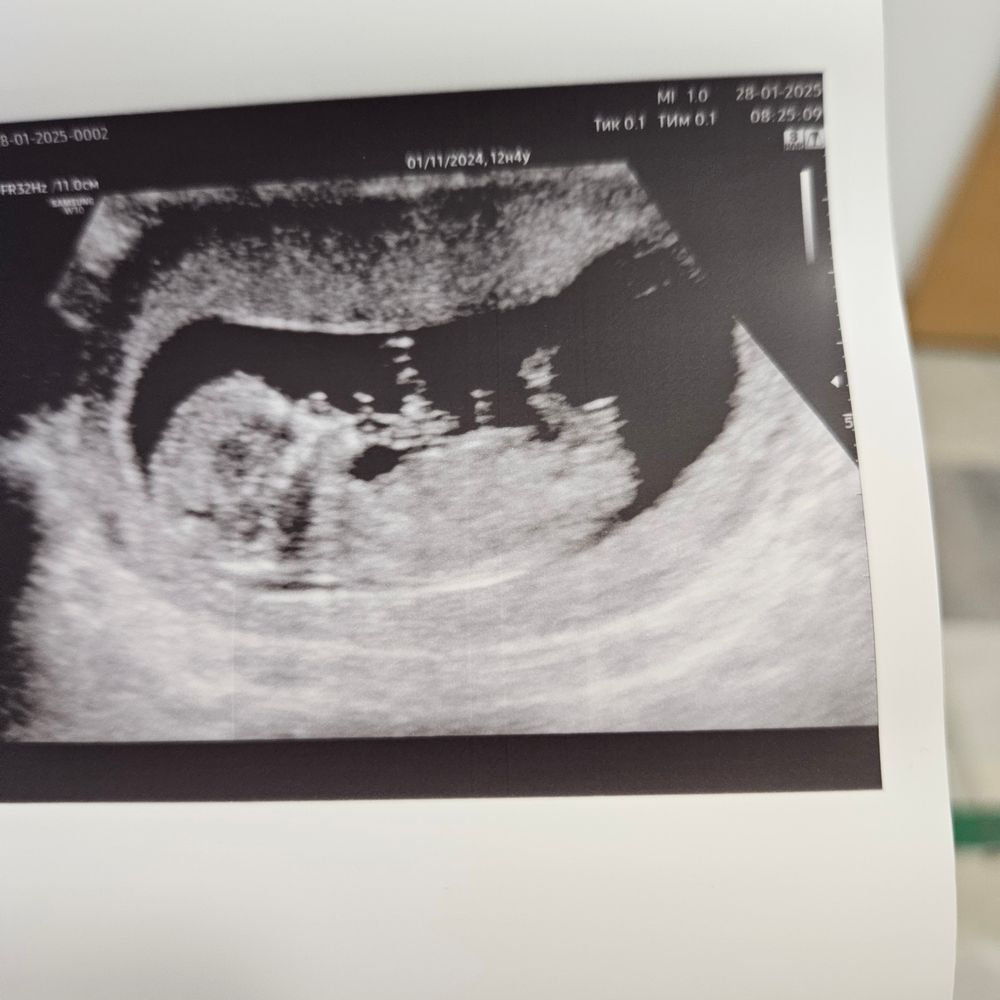

И вот наконец 12.4 - запись на 1 срининг

Срок по узи соответствует сроку по мес.

Все визуализируется, размеры все в норме🥰

Ктр 6.2. Посчитали пальчики на руках и ногах